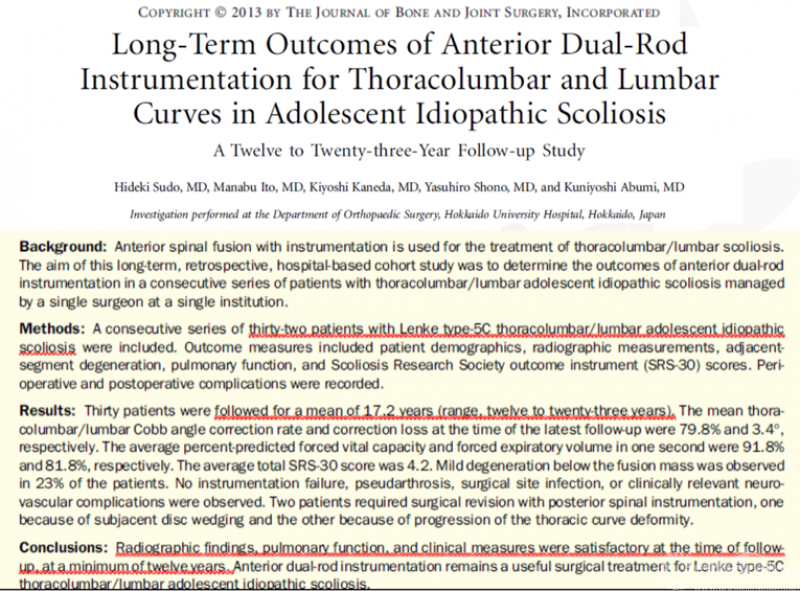

在另一篇发表在《THE JOURNAL OF BONE AND JOINT SURGERY》上对31名行前路手术的胸腰段/腰段AIS患者随访长达17.2年(12-23年)的研究中,Hideki S等人发现在影像学表现、肺功能和临床指标上前路矫正术均能获得令人满意的结果,前路双棒内固定矫正技术仍然是Lenke 5C型AIS的有效手术治疗方法[7]。

图6.引文7原文信息

7. Sudo H, Ito M, Kaneda K, Shono Y, Abumi K (2013) Long-term outcomes of anterior dual-rod instrumentation for thoracolumbar and lumbar curves in adolescent idiopathic scoliosis: a twelve to twenty-three-year follow-up study. J Bone Joint Surg Am 95:e49. doi: 10.2106/jbjs.L.00781